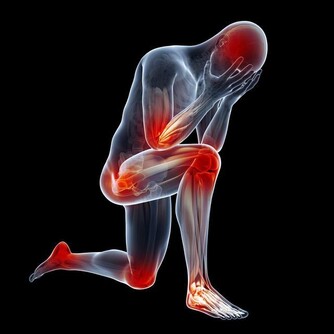

腿腳是骨骼、肌肉、關節形成的“鐵三角”,幾乎承載著身體的整個重量,僅膝蓋就承受9倍於體重的壓力。

腿腳還是交通樞紐,佈滿了人體50%的神經、50%的血管,流淌著50%的血液。

負擔過重、行動姿勢不當、寒氣侵入等都會讓腿腳受傷。另外,腿腳最容易受到傷害的地方是關節。